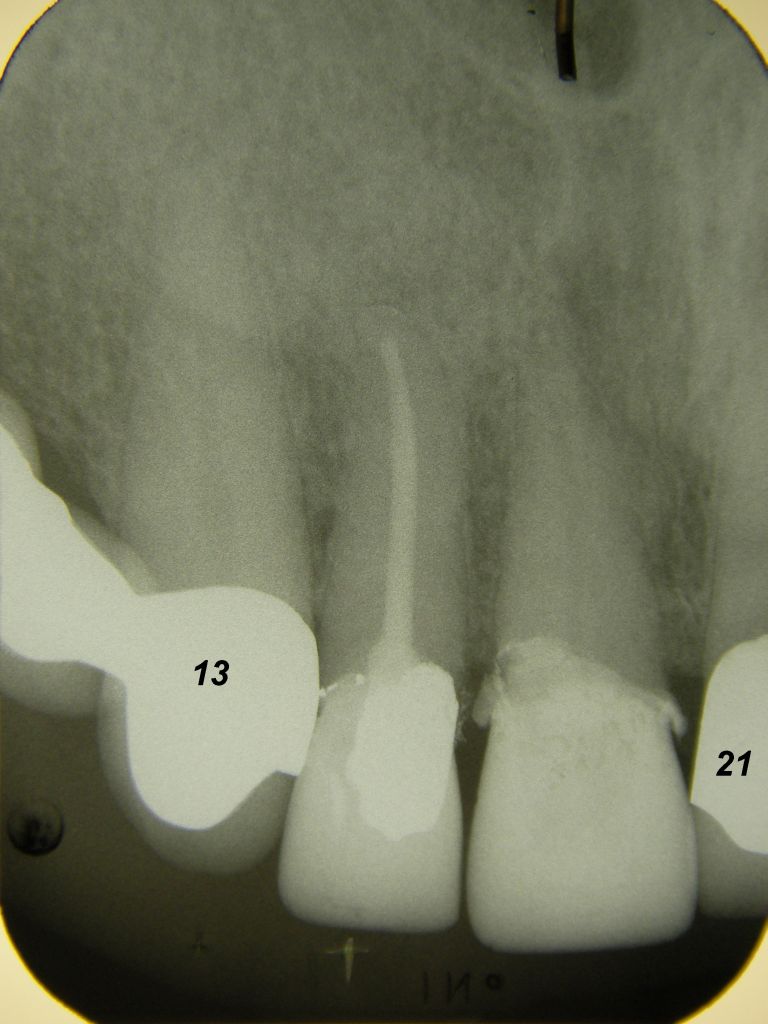

Das etwas dunkle Röntgenbild links(6/2003) zeigt diverse Probleme. Hier interessiert, daß der Zahn 22 (sprich: "zwei", "zwei") am 28.10.05 Schmerzen bereitete, weil der Zahnnerv unter Eiterbildung abgestorben war. Es brauchte 3 medikamentöse Einlagen, bis der Zahn ruhig war und am 18.11.05 eine Wurzelfüllung und einen Titanstift in den Wurzelkanal bekommen konnte. Bei der anschließenden Röntgenkontrolle rechts fiel der schlechte Randschluß der Krone 22 auf. |

Weil auch die anderen Schneidezahnkronen (12-22) durch Randreparaturen und den schlechten Randschluß erneuerungsbedürftig aussahen, wurden 4 Einzelkronen geplant. Vorher hieß es aber noch, die schlechte Wurzelfüllung im Zahn 12 (Röntgenbild links) besser zu machen. Hierfür wurden am 17.2.06 die alten Kronen 11 und 12 entfernt. Rechts das Bild nach Entfernung von alten Füllungen und Karies. | |